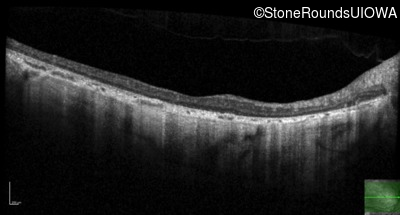

Optical Coherence Tomography - Right - 10/200 sc

Exemplar / OCT Stack

OCT Stack